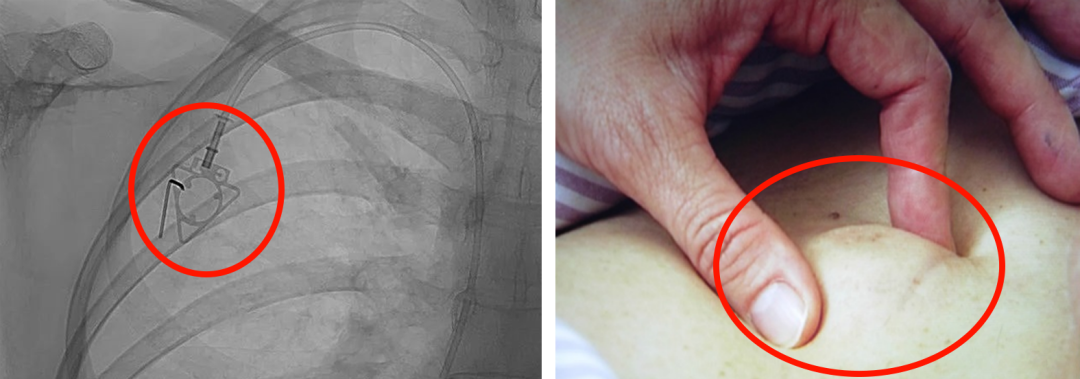

輸液港,臨床上也稱為PORT,是為了減輕藥物對患者血管刺激而置入體內(nèi)的專業(yè)輸液裝置。它分為三部分:無損傷針、置入靜脈的導管、埋藏在皮下與輸液針連接的注射座(港體)。注射座連接插入大靜脈的導管形成長期血管通路,發(fā)揮類似港口的作用,故稱作“輸液港”。

(1)輸液港輸注藥物直達大血管,手臂不會產(chǎn)生明顯的不適。由于每次穿刺的是皮下置入的港,可以減少針頭對血管的刺入次數(shù),操作簡單,對患者的血管起到保護作用;

(2)輸液港放置在皮下,不易被別人發(fā)現(xiàn),具有隱秘性;洗澡,日常生活不受限制;

(3)由于輸液港完全埋藏在體內(nèi),不易受到感染;